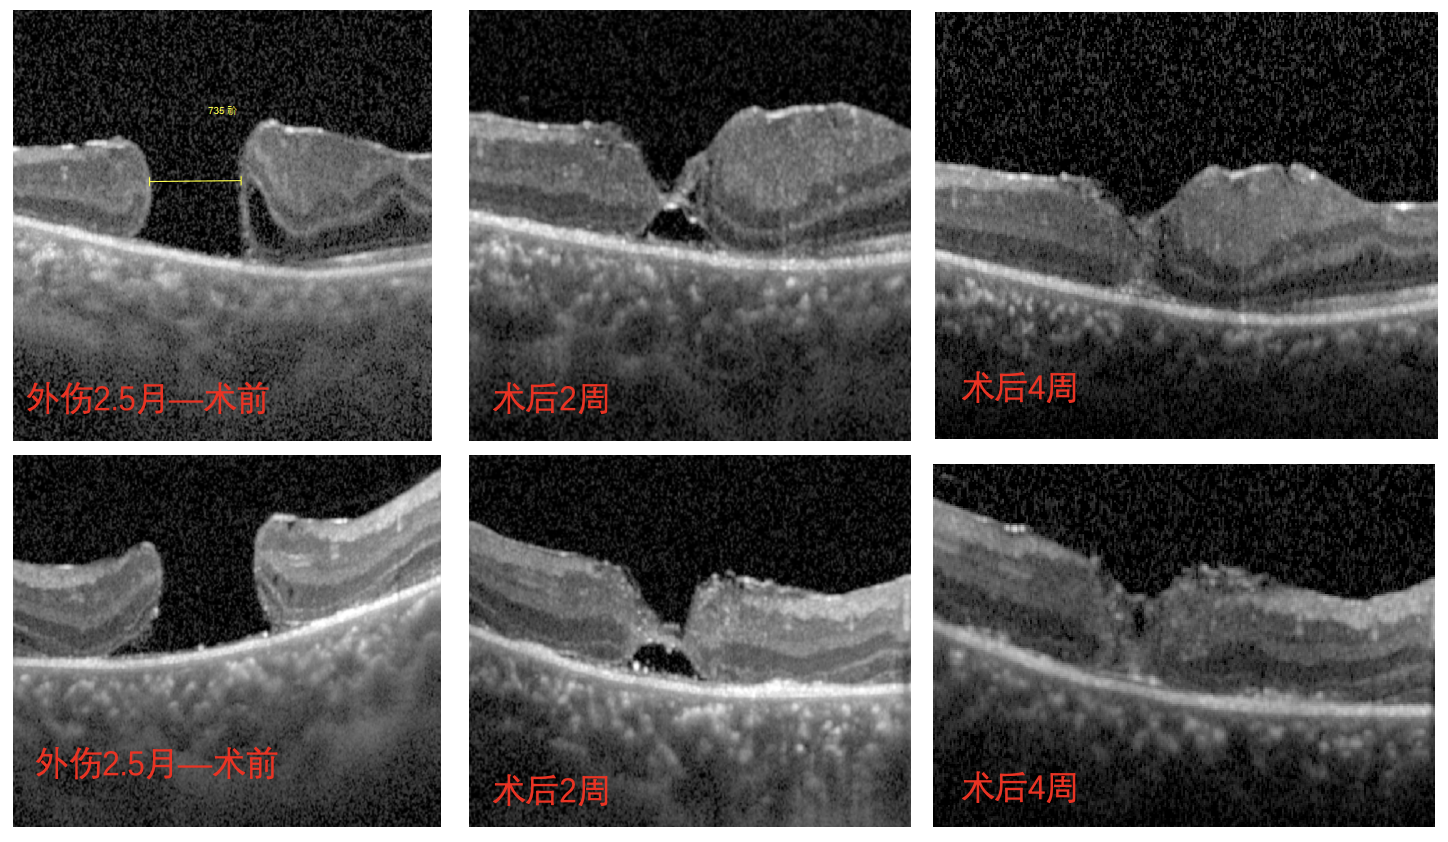

外傷黃斑裂孔術(shù)后演變成難治性黃斑裂孔,小孩千里尋醫求診挽救 “視” 界

但術(shù)后一個(gè)月復查時(shí)發(fā)現,南南的眼底恢復情況并不好,檢查時(shí)還可見(jiàn)黃斑處的裂孔,并且裂孔越來(lái)越大,演變成難治性黃斑裂孔。

經(jīng)過(guò)完善的術(shù)前檢查和評估后,李海波博士后用創(chuàng )新術(shù)式——剝除黃斑裂孔周邊殘余的內界膜組織,通過(guò)利用黏彈劑固定翻轉的內界膜瓣為南南進(jìn)行治療。術(shù)后24小時(shí)復查時(shí),南南黃斑處的裂孔已實(shí)現愈合,視力也得到了明顯的改善,現已康復出院。